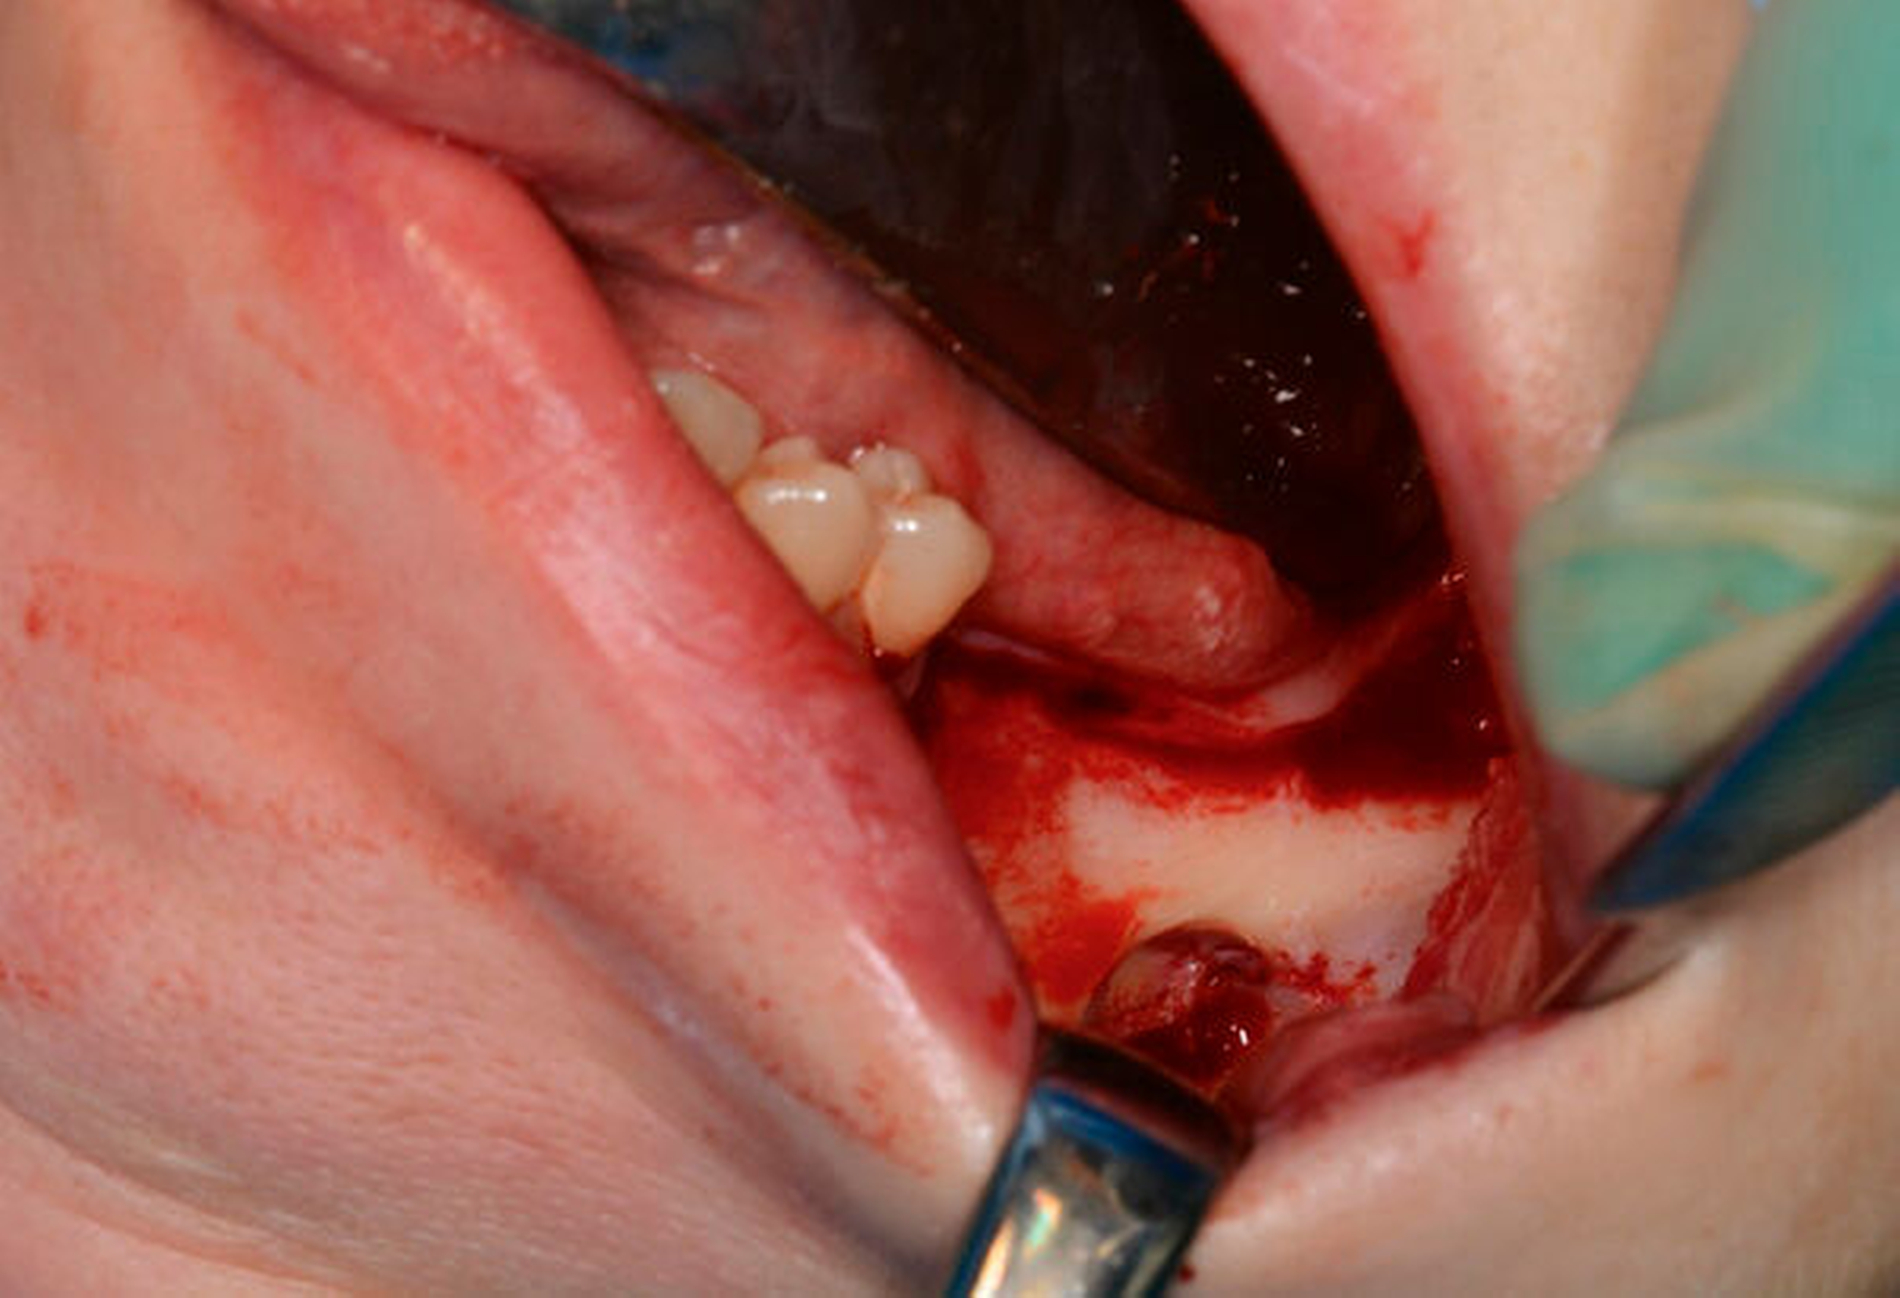

Aufgrund der tiefen intraossären Lage ohne direkten Zahnbezug oder andere klare Orientierungspunkte wurde zur gezielten Ansteuerung auf Basis des DVT-Datensatzes eine Osteotomie-Schablone 3-D-gedruckt (Material: MED 610, Drucker: EDEN 260V, Stratasys), die den Osteotomiezugang genau verschlüsselte (Abbildung 3a). Intraoperativ konnte dadurch die Keratozyste gezielt entfernt werden, ohne dass eine großflächige Osteotomie notwendig war oder ein erhöhtes Risiko für die Verletzung des N. alveolaris inferior bestand (Abbildung 3b). Der Befund wurde zystekotomiert und die Knochenhöhle zusätzlich ausgefräst (Abbildung 4). Auch die postoperative radiologische Kontrolle bestätigte eine optimale Lage der Osteotomie (Abbildung 5). Die postoperative Heilung war unproblematisch, drei Jahre nach dem Eingriff ist die Patientin rezidivfrei (Abbildung 6).